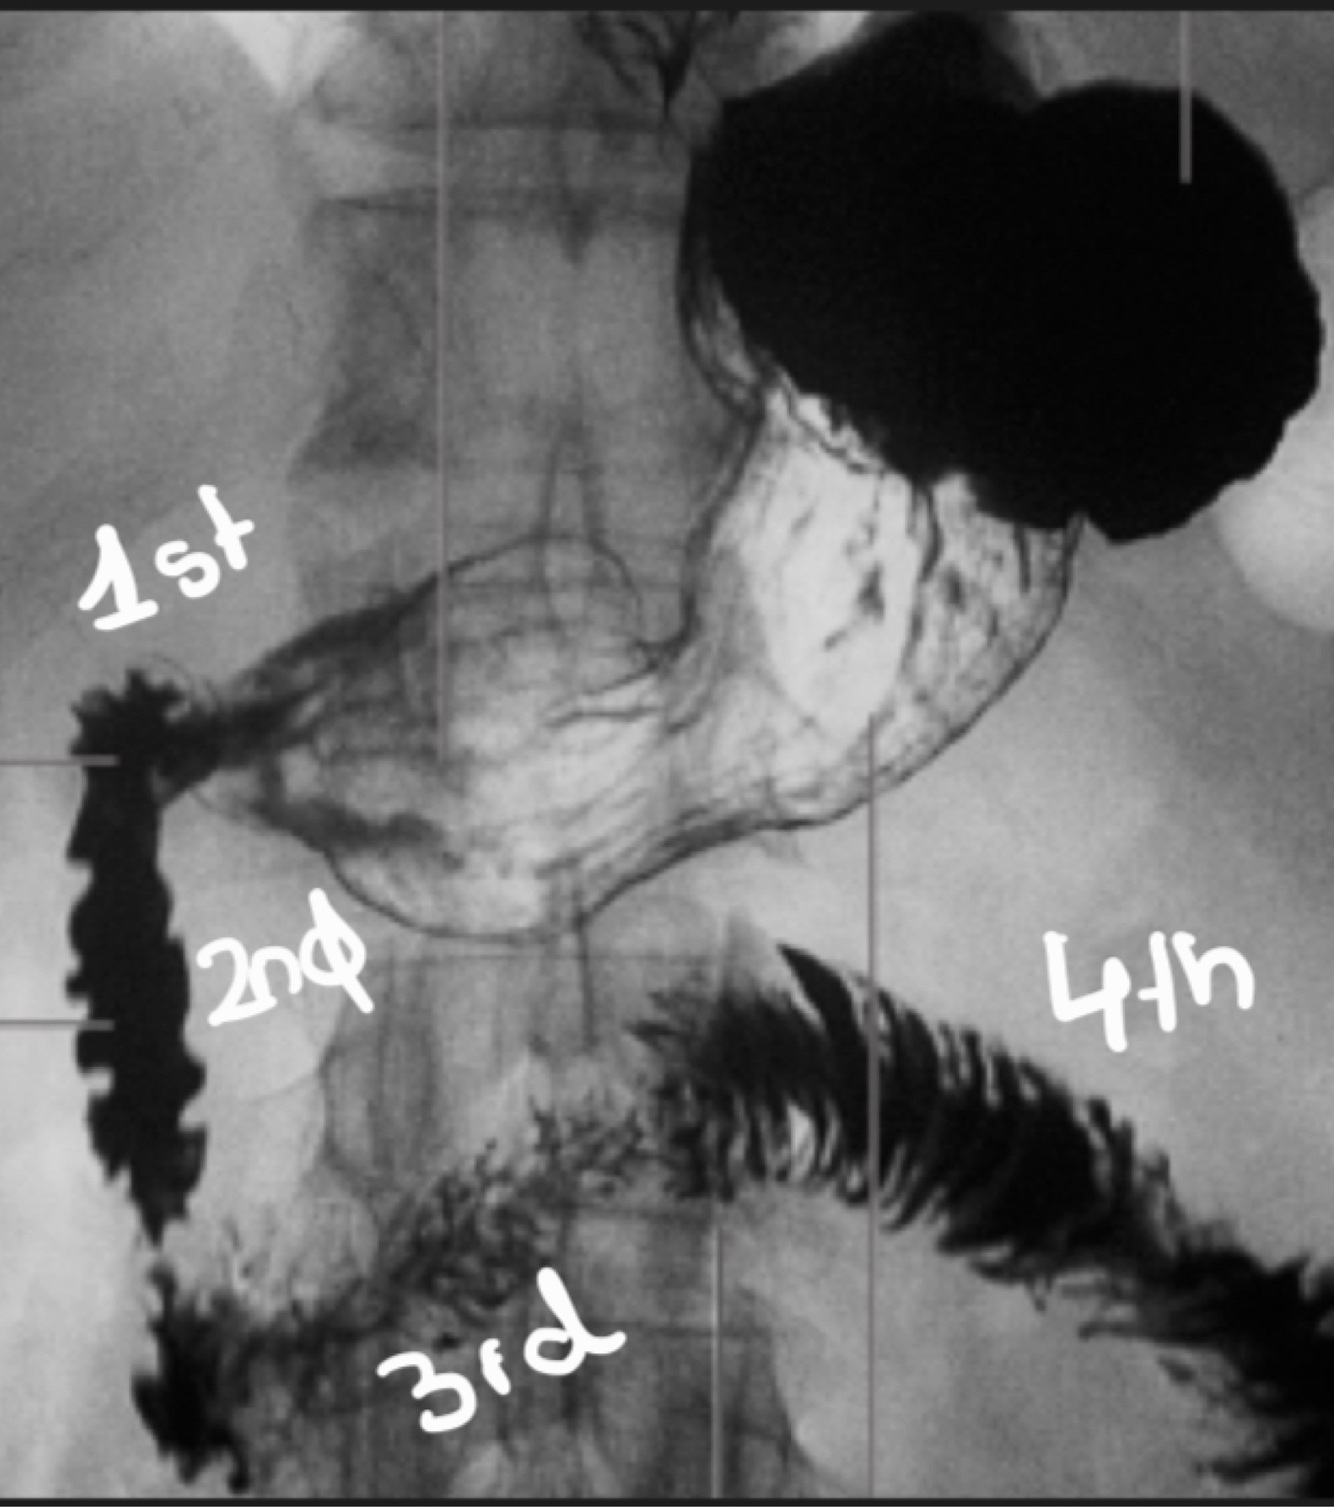

24

Parts of the duodenum

How well did you know this?

1st and 4th part of the duodenum are…, 2nd and 3rd are…

Intra peritoneal, retroperitoneal